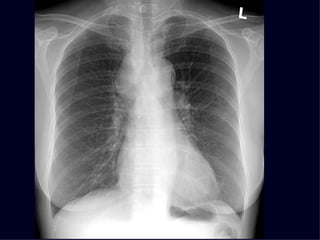

Tension Pneumothorax

hugeptx

Tracheal Deviation

Collapsed Right Lung

What would you do with this patient?

Tension Pneumothorax: Requires chest tube

hugeptx Tracheal Deviation Collapsed Right Lung What would you do with this patient? Tension Pneumothorax: Requires chest tube